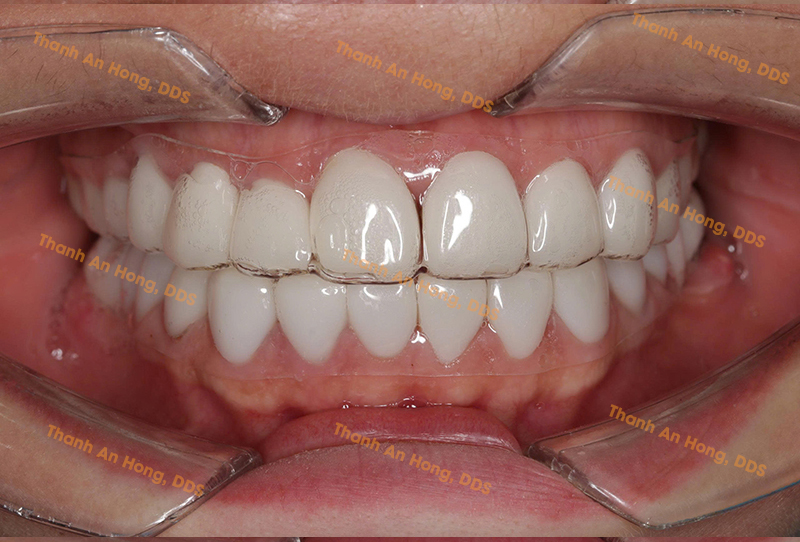

HÌNH ẢNH THỰC TẾ

Khay trong suốt chỉnh lệch đường giữa với toàn hàm là răng sứ